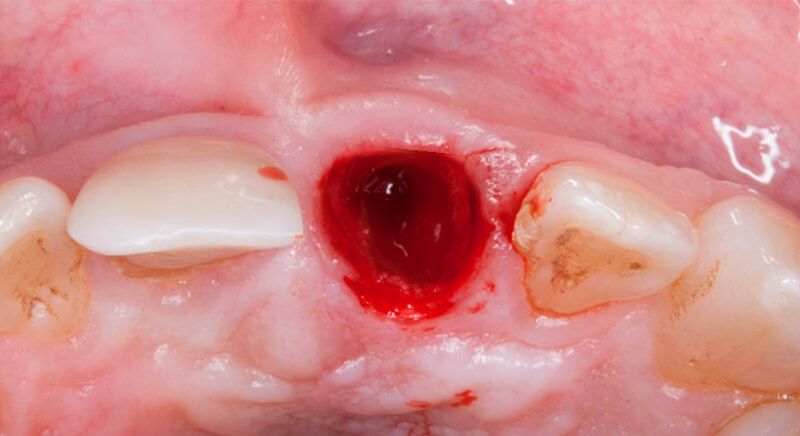

Once tooth 2.1 had been extracted, it was decided that it was not advisable to place an implant immediately as the bone conditions were not ideal and the gum did not have sufficient thickness. We opted for a treatment to preserve the socket and to delay implant insertion.

The socket was filled with a xenograft after the extraction and a graft of connective tissue was placed in the vestibular area of the two upper central incisors.